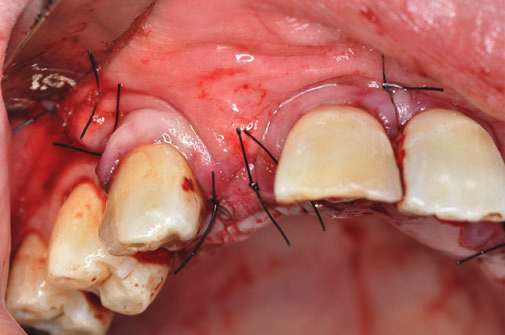

GBR法では、骨の不足している部分に人工骨の粉末を入れ、骨の再生を誘導します。

GBR法で骨を造り、その後にインプラント手術を行います。

GBR法の手術の流れを写真でご紹介しています。

どのような手術を行うのか、事前に知っていただけたらと思います。